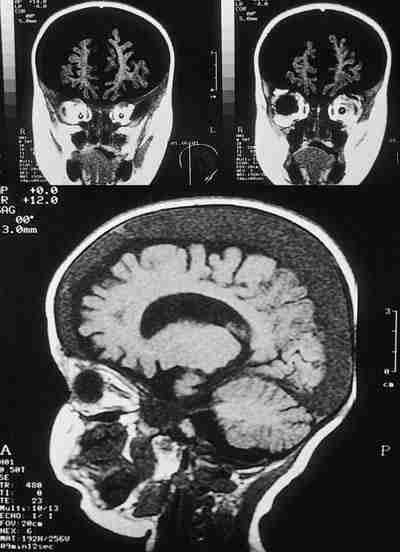

El diagnóstico del síndrome es difícil debido, por un lado, a la escasez de signos externos, y por otro, a que los padres o el cuidador raras veces admiten haber maltratado al niño. Por ello, ante la sospecha de maltrato infantil, es fundamental realizar un examen de la retina y un TAC y/o RMN cerebral (91,92,100). Cabe destacar que el examen oftalmológico puede predecir el daño neurológico, ya que se ha encontrado correlación entre la severidad de la hemorragia retiniana (afectación retiniana difusa, hemorragia vítrea o extensas hemorragias subhialoideas) y el pronóstico de las lesiones cerebrales (100-105). La ceguera, el retraso mental y la muerte, son secuelas comunes en este síndrome. La muerte suele ocurrir en muchos casos asociada a aumento incontrolado de la presión intracraneal. Las causas más frecuentes de pérdida de visión son los pliegues maculares y las lesiones corticales (106,107). El diagnóstico diferencial incluye: traumatismos durante el parto, alteraciones hematológicas como anemia severa, trombocitopenia, leucemia aguda y coagulopatías y hemorragias tras la resucitación cardiopulmonar (98).